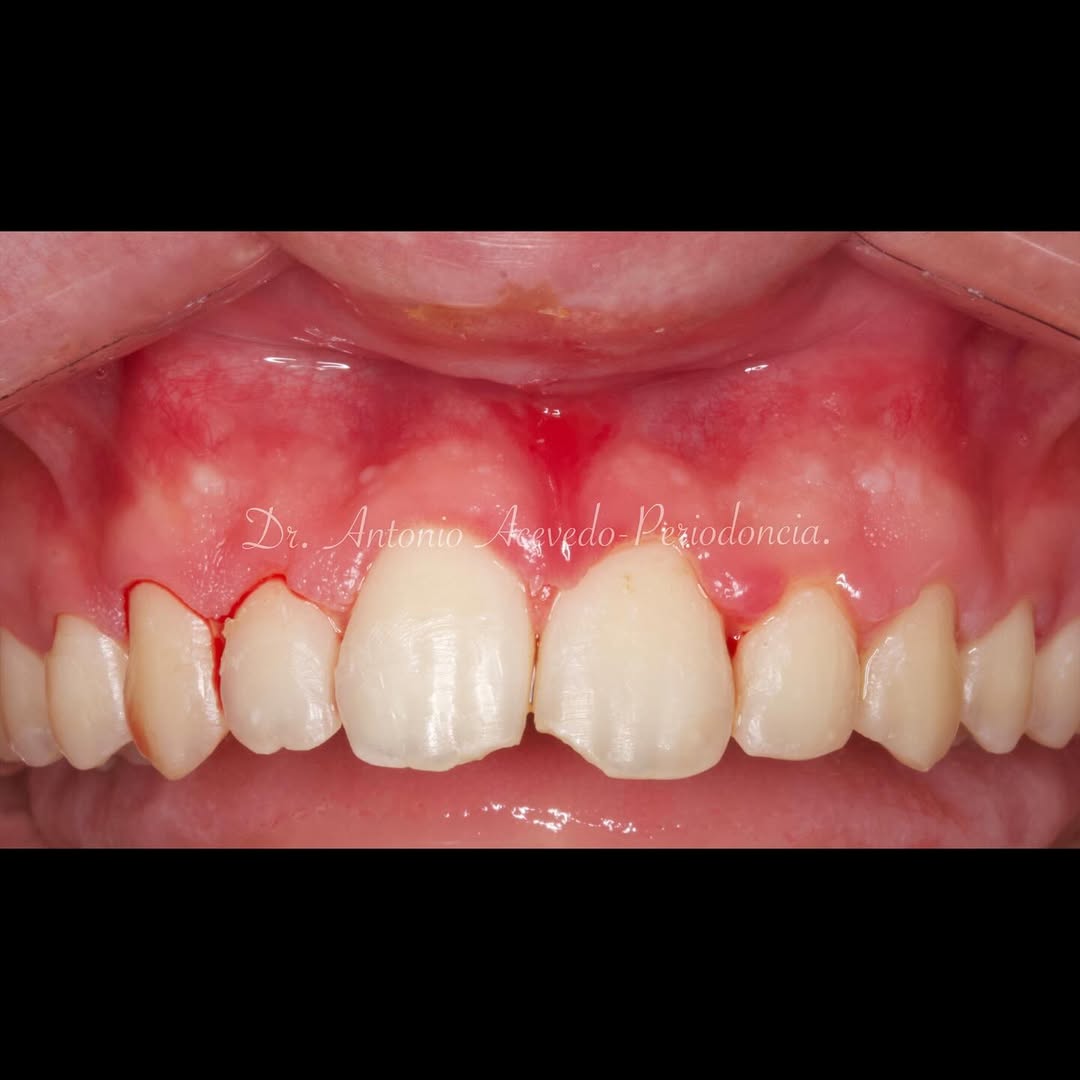

Una estancia clínica pensada para quienes quieran iniciarse o dar un paso más en el campo de la cirugía mucogingival. Durante esta experiencia tendrás la oportunidad de aprender en directo cómo

Una estancia clínica pensada para quienes quieran iniciarse o dar un paso más en el campo de la cirugía mucogingival. Durante esta experiencia tendrás la oportunidad de aprender en directo cómo se planifica y se lleva a cabo una cirugía mucogingival mediante técnica de Túnel.

La sesión